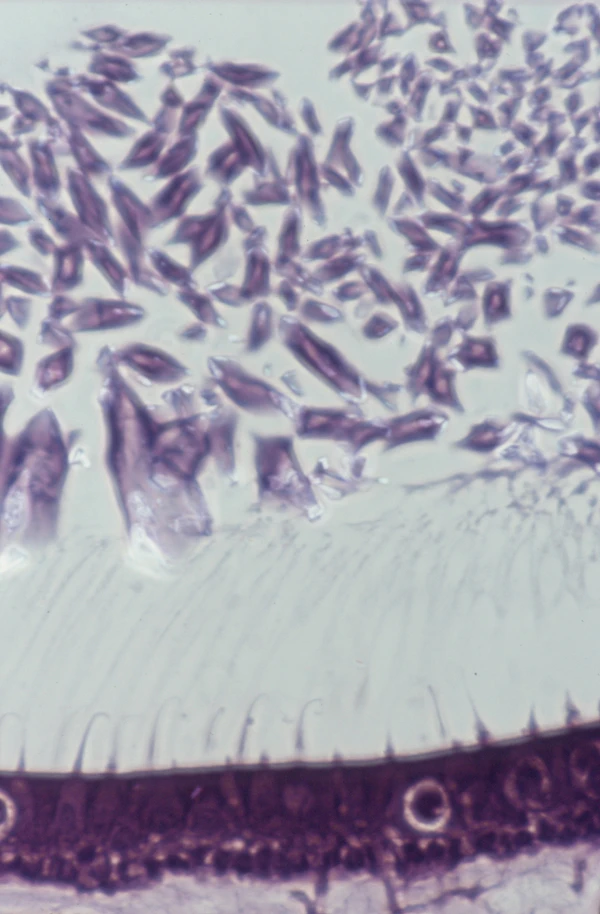

Отолиты — микроскопические кристаллы карбоната кальция, которые находятся в преддверии внутреннего уха и отсутствуют в полукружных каналах. В силу разных причин отолиты отрываются от своей мембраны и попадают в полукружные каналы. При наклоне головы меняется положение канала, и отолиты в нем начинают перемещаться под действием силы тяжести. Их движение и провоцирует ощущение головокружения. Через несколько секунд отолиты останавливаются в самой нижней точке, и головокружение прекращается.